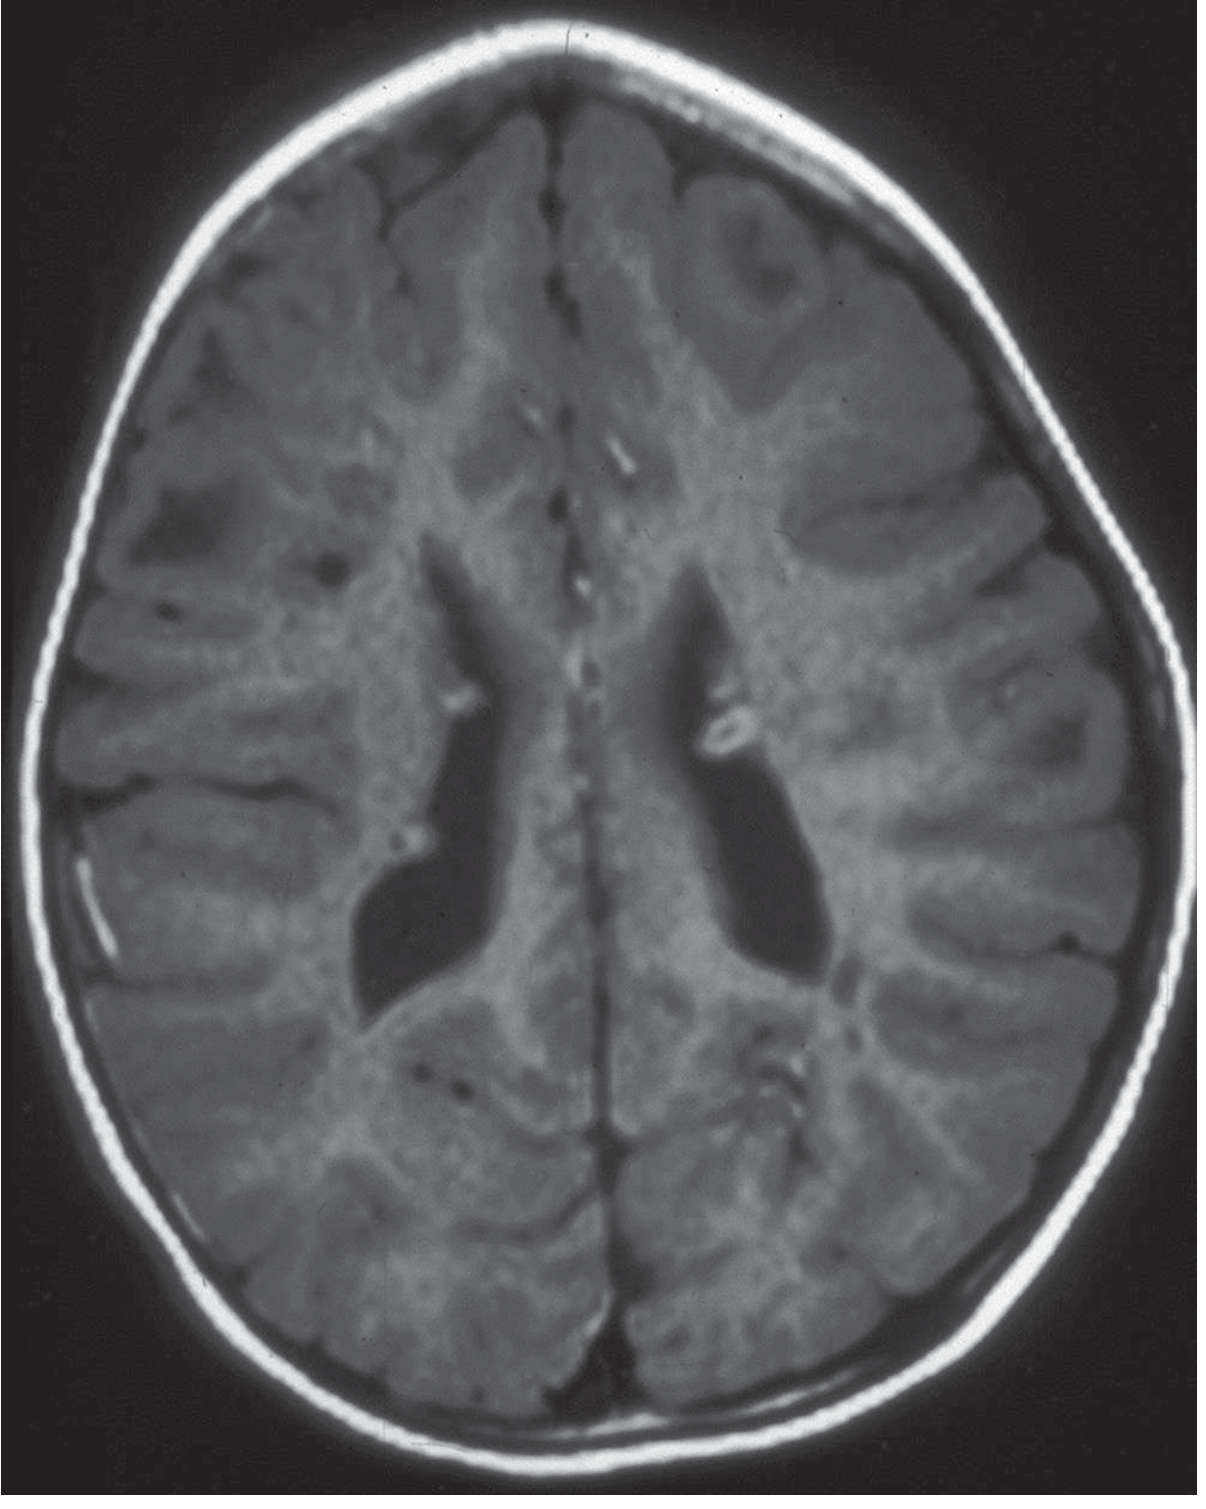

| MRI brain | Detect cortical tubers, subependymal nodules, SEGA (detectable as early as 6 weeks) |

| Finding | MRI Appearance |

|---|---|

| Cortical tubers | Hypointense on T1, hyperintense on T2/FLAIR; expand gyri; may calcify |

| Subependymal nodules (SEN) | "Candle drippings" along ventricular walls; calcify over time → hypointense on T2 |

| Subependymal giant cell astrocytoma (SEGA) | Enhancing mass at foramen of Monro; >1 cm, growing → urgent treatment |

| White matter radial migration lines | T2-hyperintense lines radiating from ventricle to cortex |

| Hydrocephalus | May occur if SEGA obstructs CSF flow |

Note: CT or cranial ultrasound (in infants with open fontanelles) is suboptimal but acceptable if MRI is not available. CT detects calcified nodules well but misses early/uncalcified tubers. MRI detects lesions as early as 6 weeks of age.